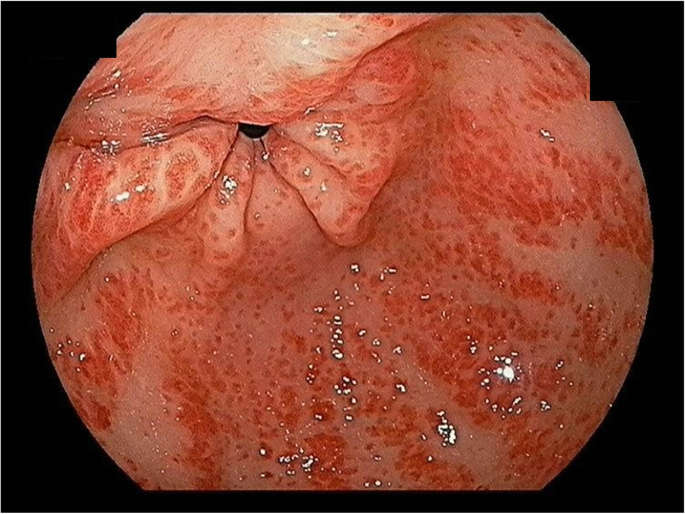

After 5 months from initiation of HD, hemoglobin level suddenly dropped to 5.5 g/dL and the patient complaint of dizziness and did not have change in stool nature. The anemia was evaluated using the iron status, peripheral blood (PB) smear, and GFS. Iron, transferrin saturation, and ferritin levels were 46 μg/dL, 18.5%, and 448.5 ng/mL (reference level: 5–205 ng/mL), respectively. The PB smear revealed a normocytic normochromic anemia. GFS revealed multiple erythematous raised hyperemic mucosal lesions at the distal antrum without active bleeding (Fig. 1), a finding compatible with GAVE. Anti-ulcer treatment was started using a proton pump inhibitor. Although the patient was diagnosed with GAVE, the patient did not have active bleeding focus and melena. We performed bone marrow biopsy because the definite cause of anemia was not identified. The bone marrow biopsy showed a normocellular marrow with normal iron status. Hemoglobin level was stable after transfusion and anemia did not recur.